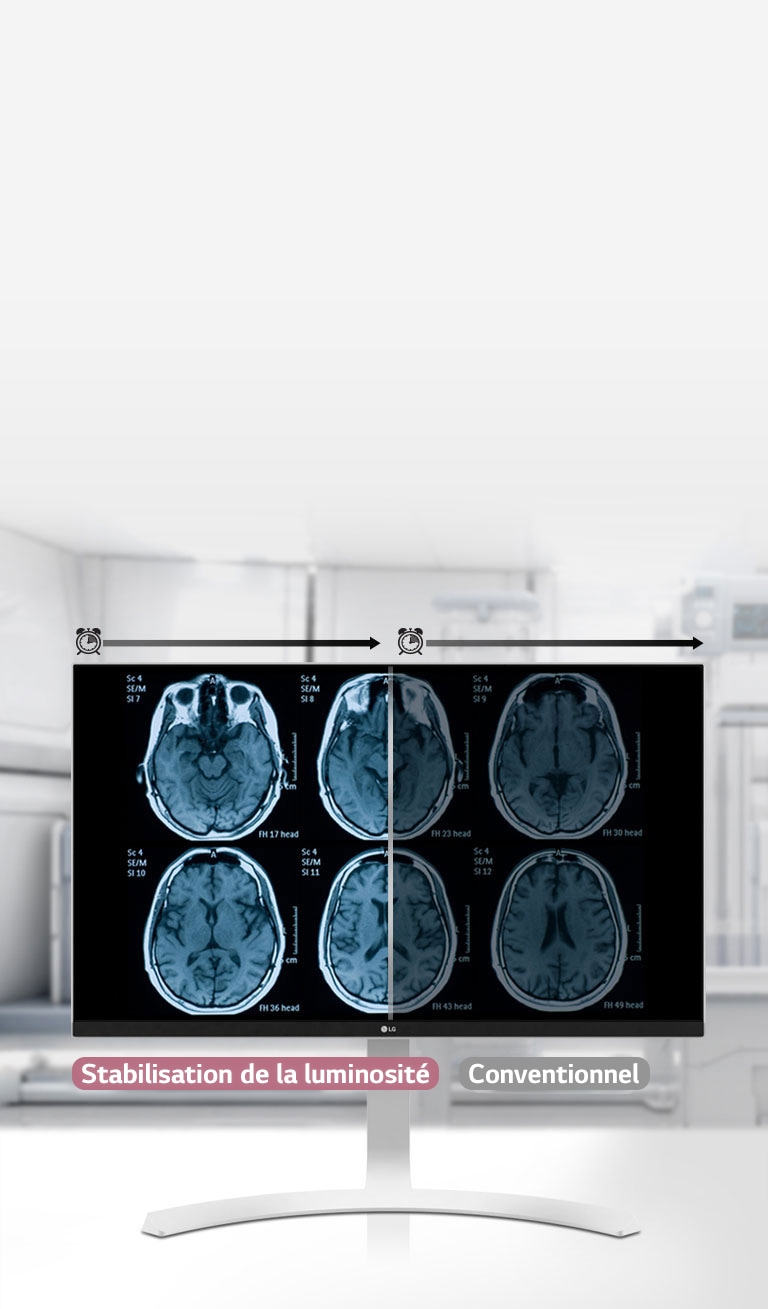

Stabilisation de la luminosité

OUI